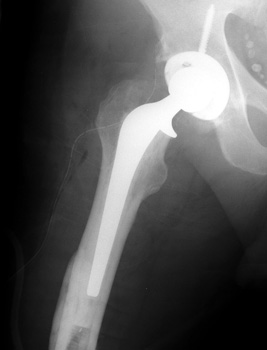

Cement extravasation in the thigh through intraoperative

fracture at the level of the tip of the femoral stem.